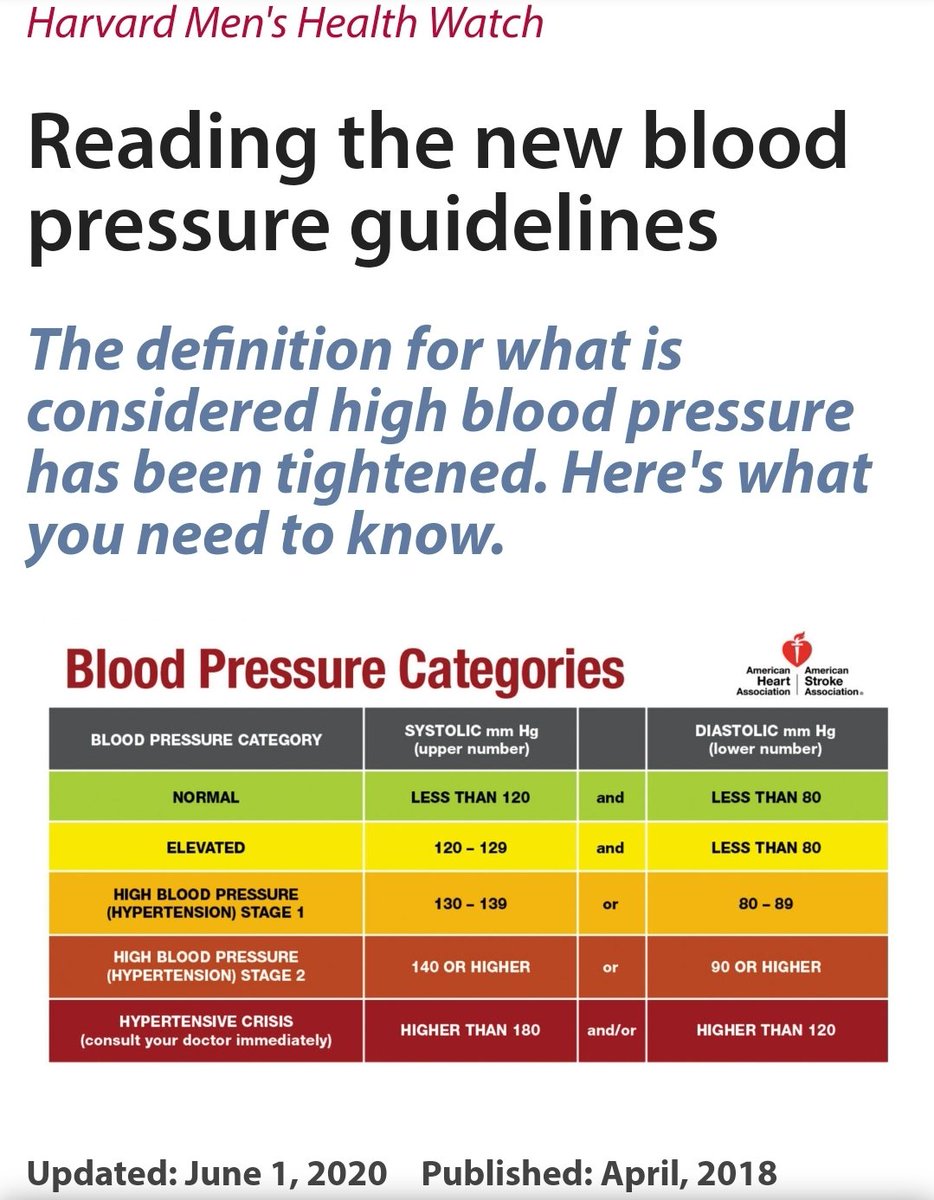

🧠ارتفاع ضغط الدم بشكل مفاجئ

🧠ارتفاع ضغط الدم بشكل مفاجئ

💥السيطرة ع #ضغط_الدم

💥السيطرة ع #ضغط_الدم

🧠ارتفاع الضغط

🧠ارتفاع الضغط